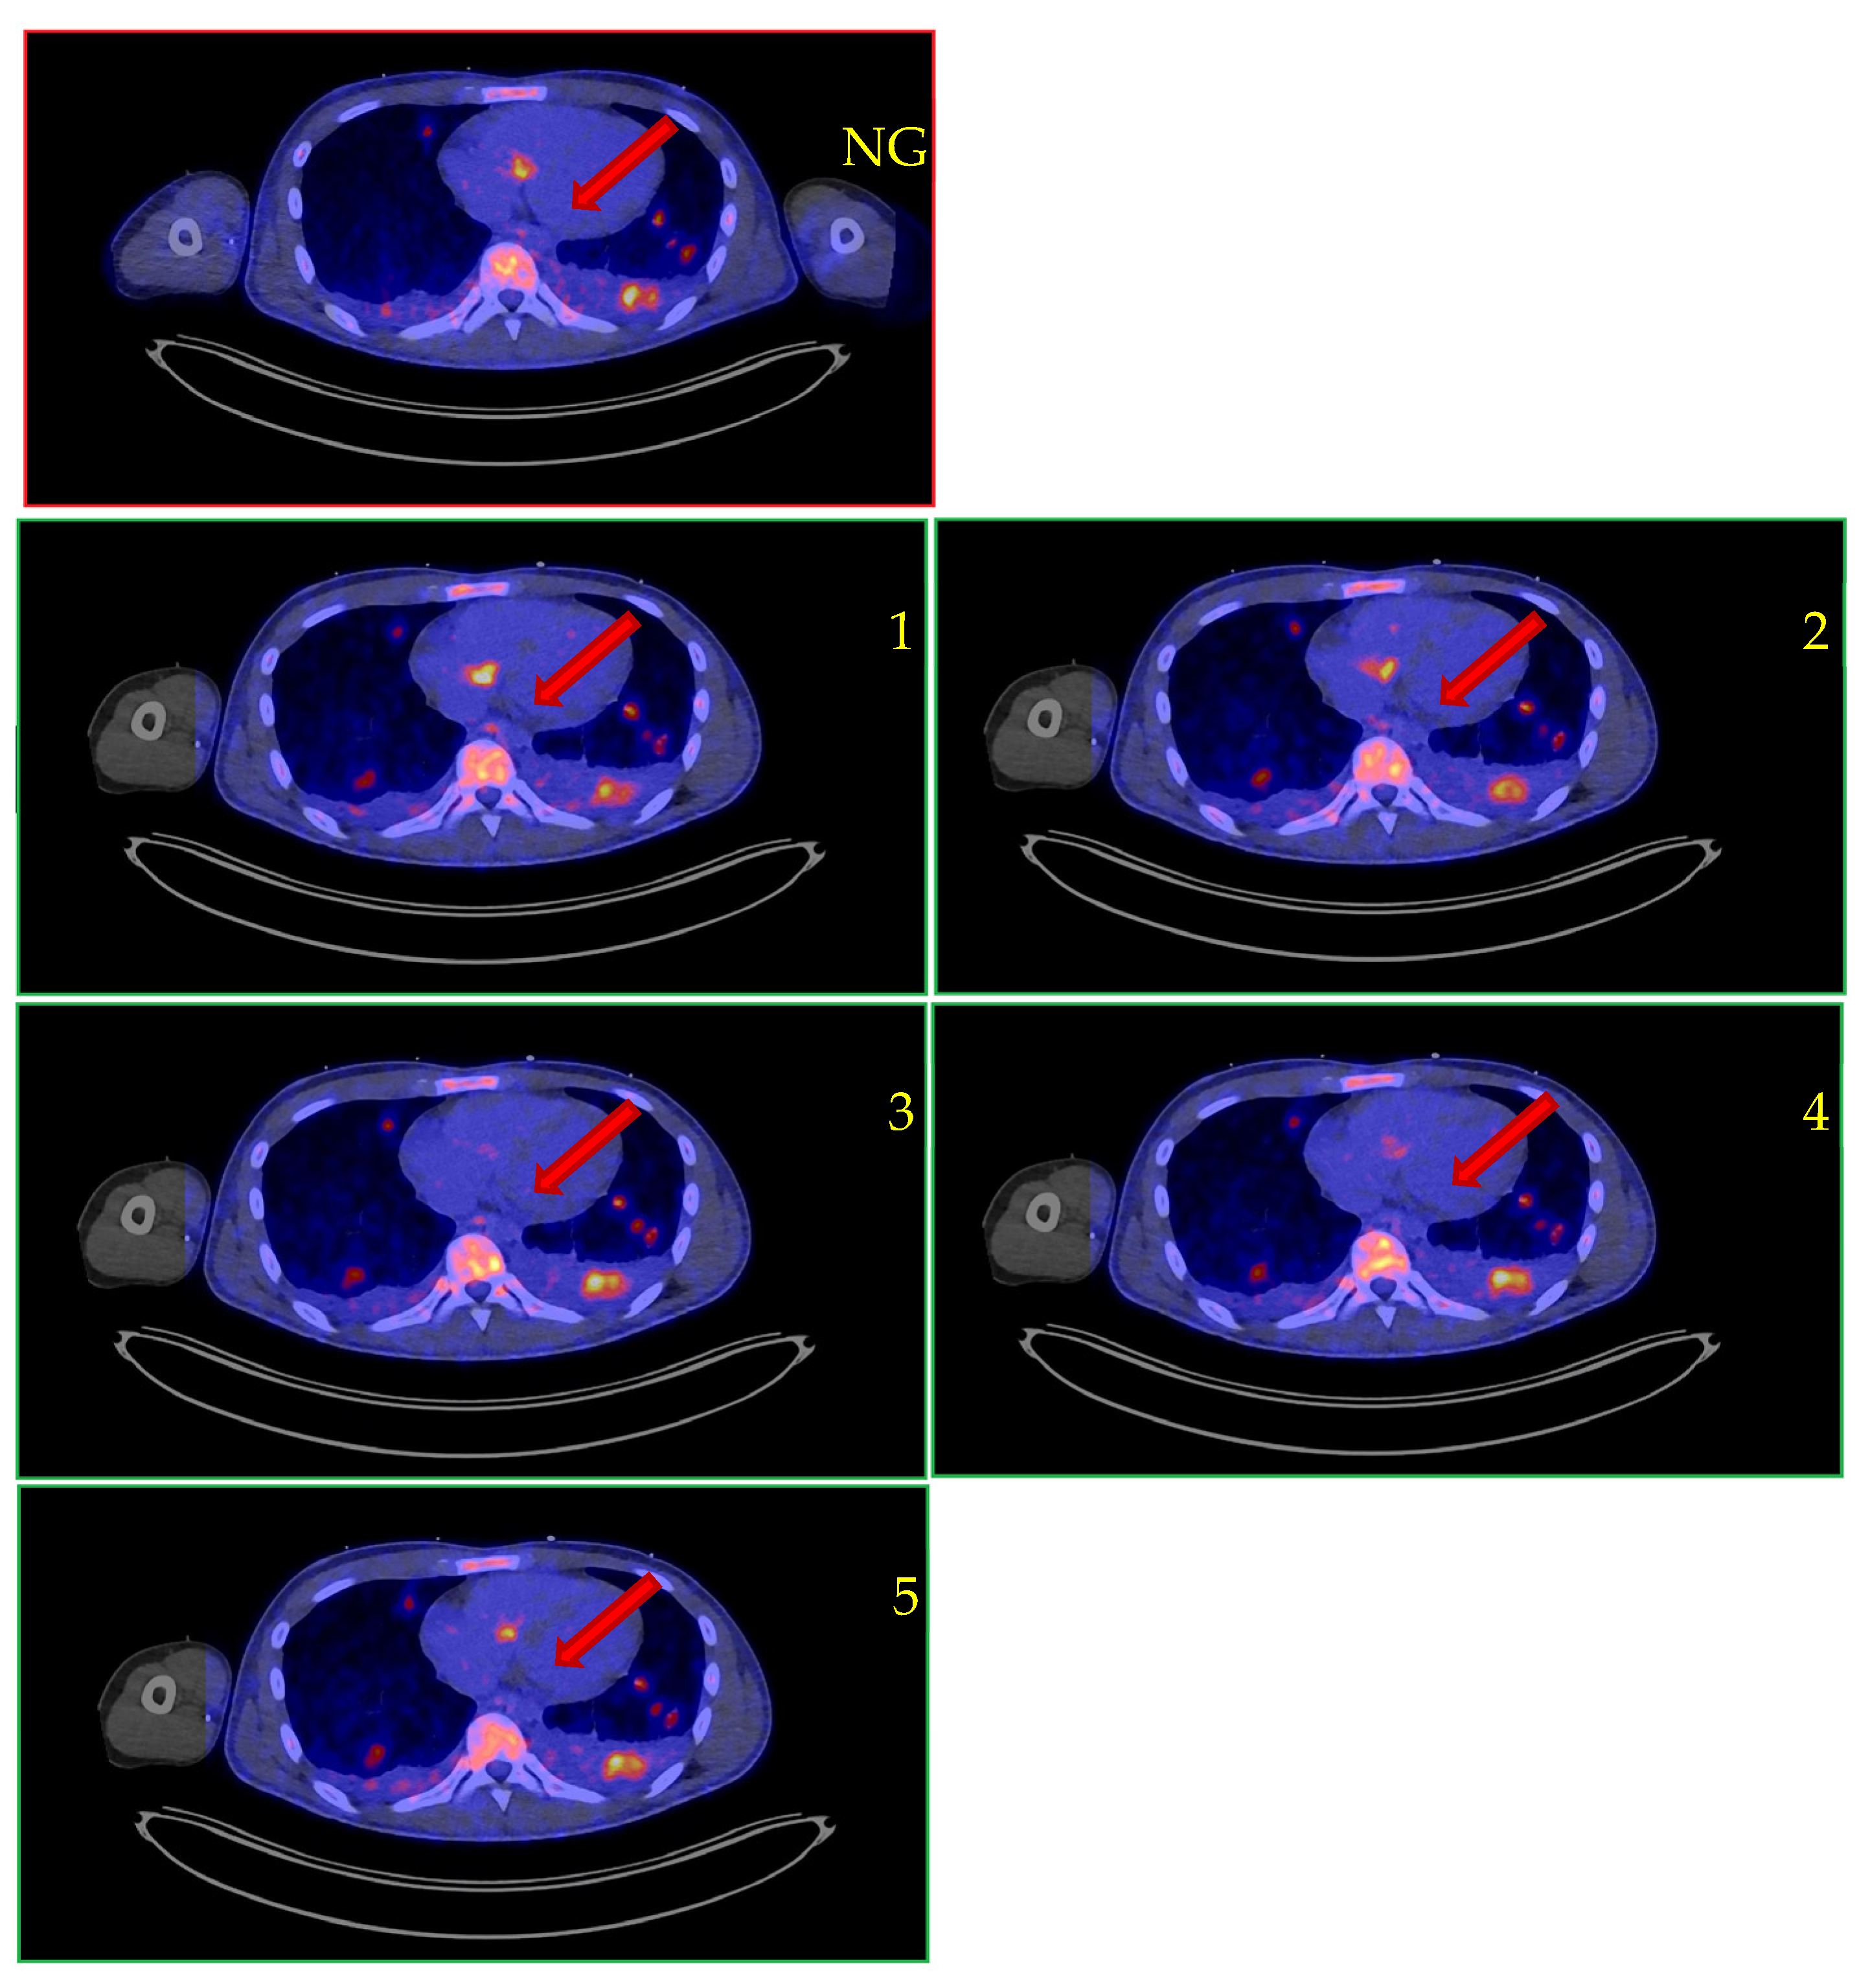

| PET results | Non-gated: IE confirmed Gated: Not available CardioFreezeTM: IE confirmed (fl+) | Non-gated: No IE Gated: No IE CardioFreezeTM: No IE | Non-gated: IE confirmed Gated: IE confirmed (fl+) CardioFreezeTM: Not available | Non-gated: Equivocal Gated: Equivocal CardioFreezeTM: Not available | Non-gated: No IE Gated: Not available CardioFreezeTM: IE confirmed | Non-gated: No IE Gated: Not available CardioFreezeTM: No IE | Non-gated: IE confirmed Gated: IE confirmed (fl+) CardioFreezeTM: IE confirmed (fl+) |